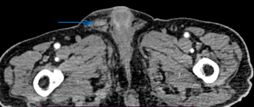

Evident dilation of the left ureter -- yellow outline. Green outline -- Chordoma (Courtesy Dr. V. Penopoulos)